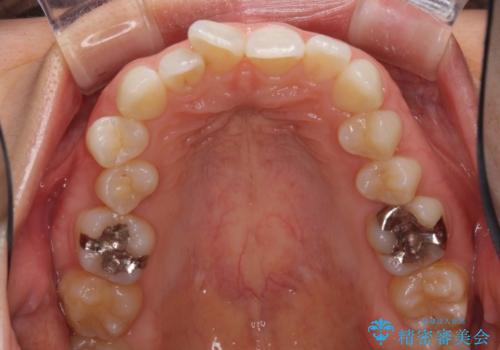

深い咬み合わせと奥歯のむし歯 総合歯科治療

- 奥歯の虫歯と前歯のデコボコや突出感を気にして来院された患者様です。

矯正治療後は、奥歯の虫歯や銀歯を補綴・修復治療することとしました。